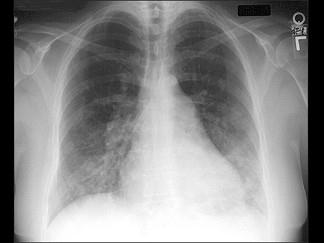

问题 室间隔缺损伴明显肺动脉高压时,如图,其临床表现应除外下列哪一项 ( )

选项 A、肺动脉段明显突出 B、右室压力显著升高 C、原有心脏杂音明显增强 D、肺动脉第二音显著亢进 E、右向左分流,出现青紫

答案 C